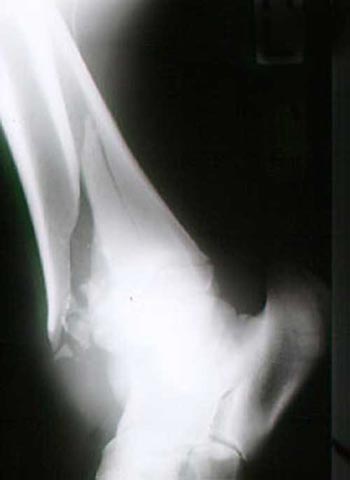

Fraktur des Unterschenkels.